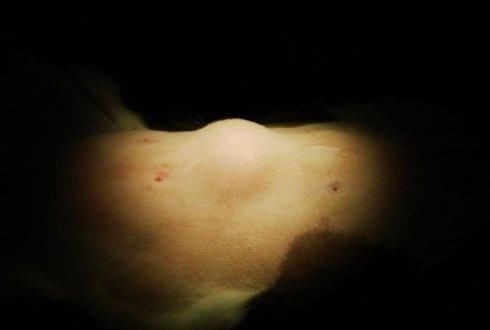

什么是脂肪瘤啊?说白了,就是我们在皮肤下面的一个包,摸起来软软的,不疼不硬,不红不肿,是非常常见的良性肿瘤。躯干和四肢的表皮下最多见。一般情况下,这玩意儿的直径不会超过5厘米。